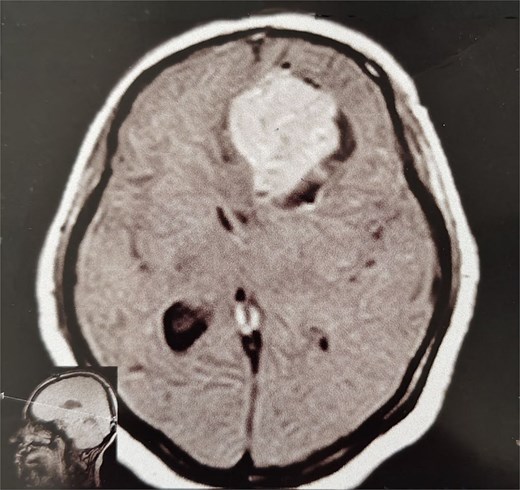

A 44-year-old right-handed woman presented with a two-month history of headache and blurred vision. Her medical history included hypertension and type 1 diabetes mellitus. She reported gradually worsening intermittent headache and bilateral visual blurring, more pronounced in the right eye. Symptoms exacerbated with physical exertion and were unrelieved by analgesics, leading to her referral. Examination revealed a conscious, alert patient with right eye proptosis. Visual acuity was 6/6 (left eye) and 6/9 (right eye). Fundoscopy identified bilateral Grade 3 papilledema. Non-contrast brain CT demonstrated a well-defined, isodense, dural-based extra-axial lesion in the left frontal region with a cystic component, measuring approximately 5.5 × 4.3 × 4.2 cm. It was associated with mild perilesional edema, mass effect, and a subtle contralateral falx shift. The initial impression was an atypical meningioma (Fig. 1). Subsequent MRI confirmed a large, falcine-based lesion that appeared isointense on T1- (Fig. 2) and T2-weighted images, demonstrating intense homogeneous enhancement post-contrast (Fig. 3). Signal voids suggested calcifications. The patient underwent gross total excision via a bilateral frontal craniotomy. The tumor was intradural and extra-axial, elevating the frontal lobe and was easily accessible; therefore, neither neuronavigation nor other intra-operative localization aids were utilized. Intraoperatively, the olfactory tract could not be clearly identified. A gap in the anterior cranial base was noted, but as there was no evidence of dural invasion or cerebrospinal fluid leak, no sealant was required. Gross examination of the resected specimen revealed a well-circumscribed, white nodule. Microscopically, sections showed benign spindle cell proliferation with alternating Antoni A and Antoni B areas (Fig. 4). Antoni A regions displayed nuclear palisading and Verocay bodies (Fig. 5), while Antoni B areas were edematous and myxoid (Fig. 6). No mitotic figures or atypia were seen. The definitive diagnosis was a benign olfactory groove schwannoma, notable given the initial radiological suspicion of meningioma. Her postoperative course was uneventful. A postoperative non-contrast CT brain obtained 48 hours after surgery confirmed gross total resection (Fig. 7). She was discharged with scheduled follow-up to monitor recovery and visual symptoms.

MRI brain without IV contrast (T1 sequence) showing a well-circumscribed hypointense mass with areas of heterogeneity occupying the right frontal lobe, closely related to the midline structures and falx cerebri.